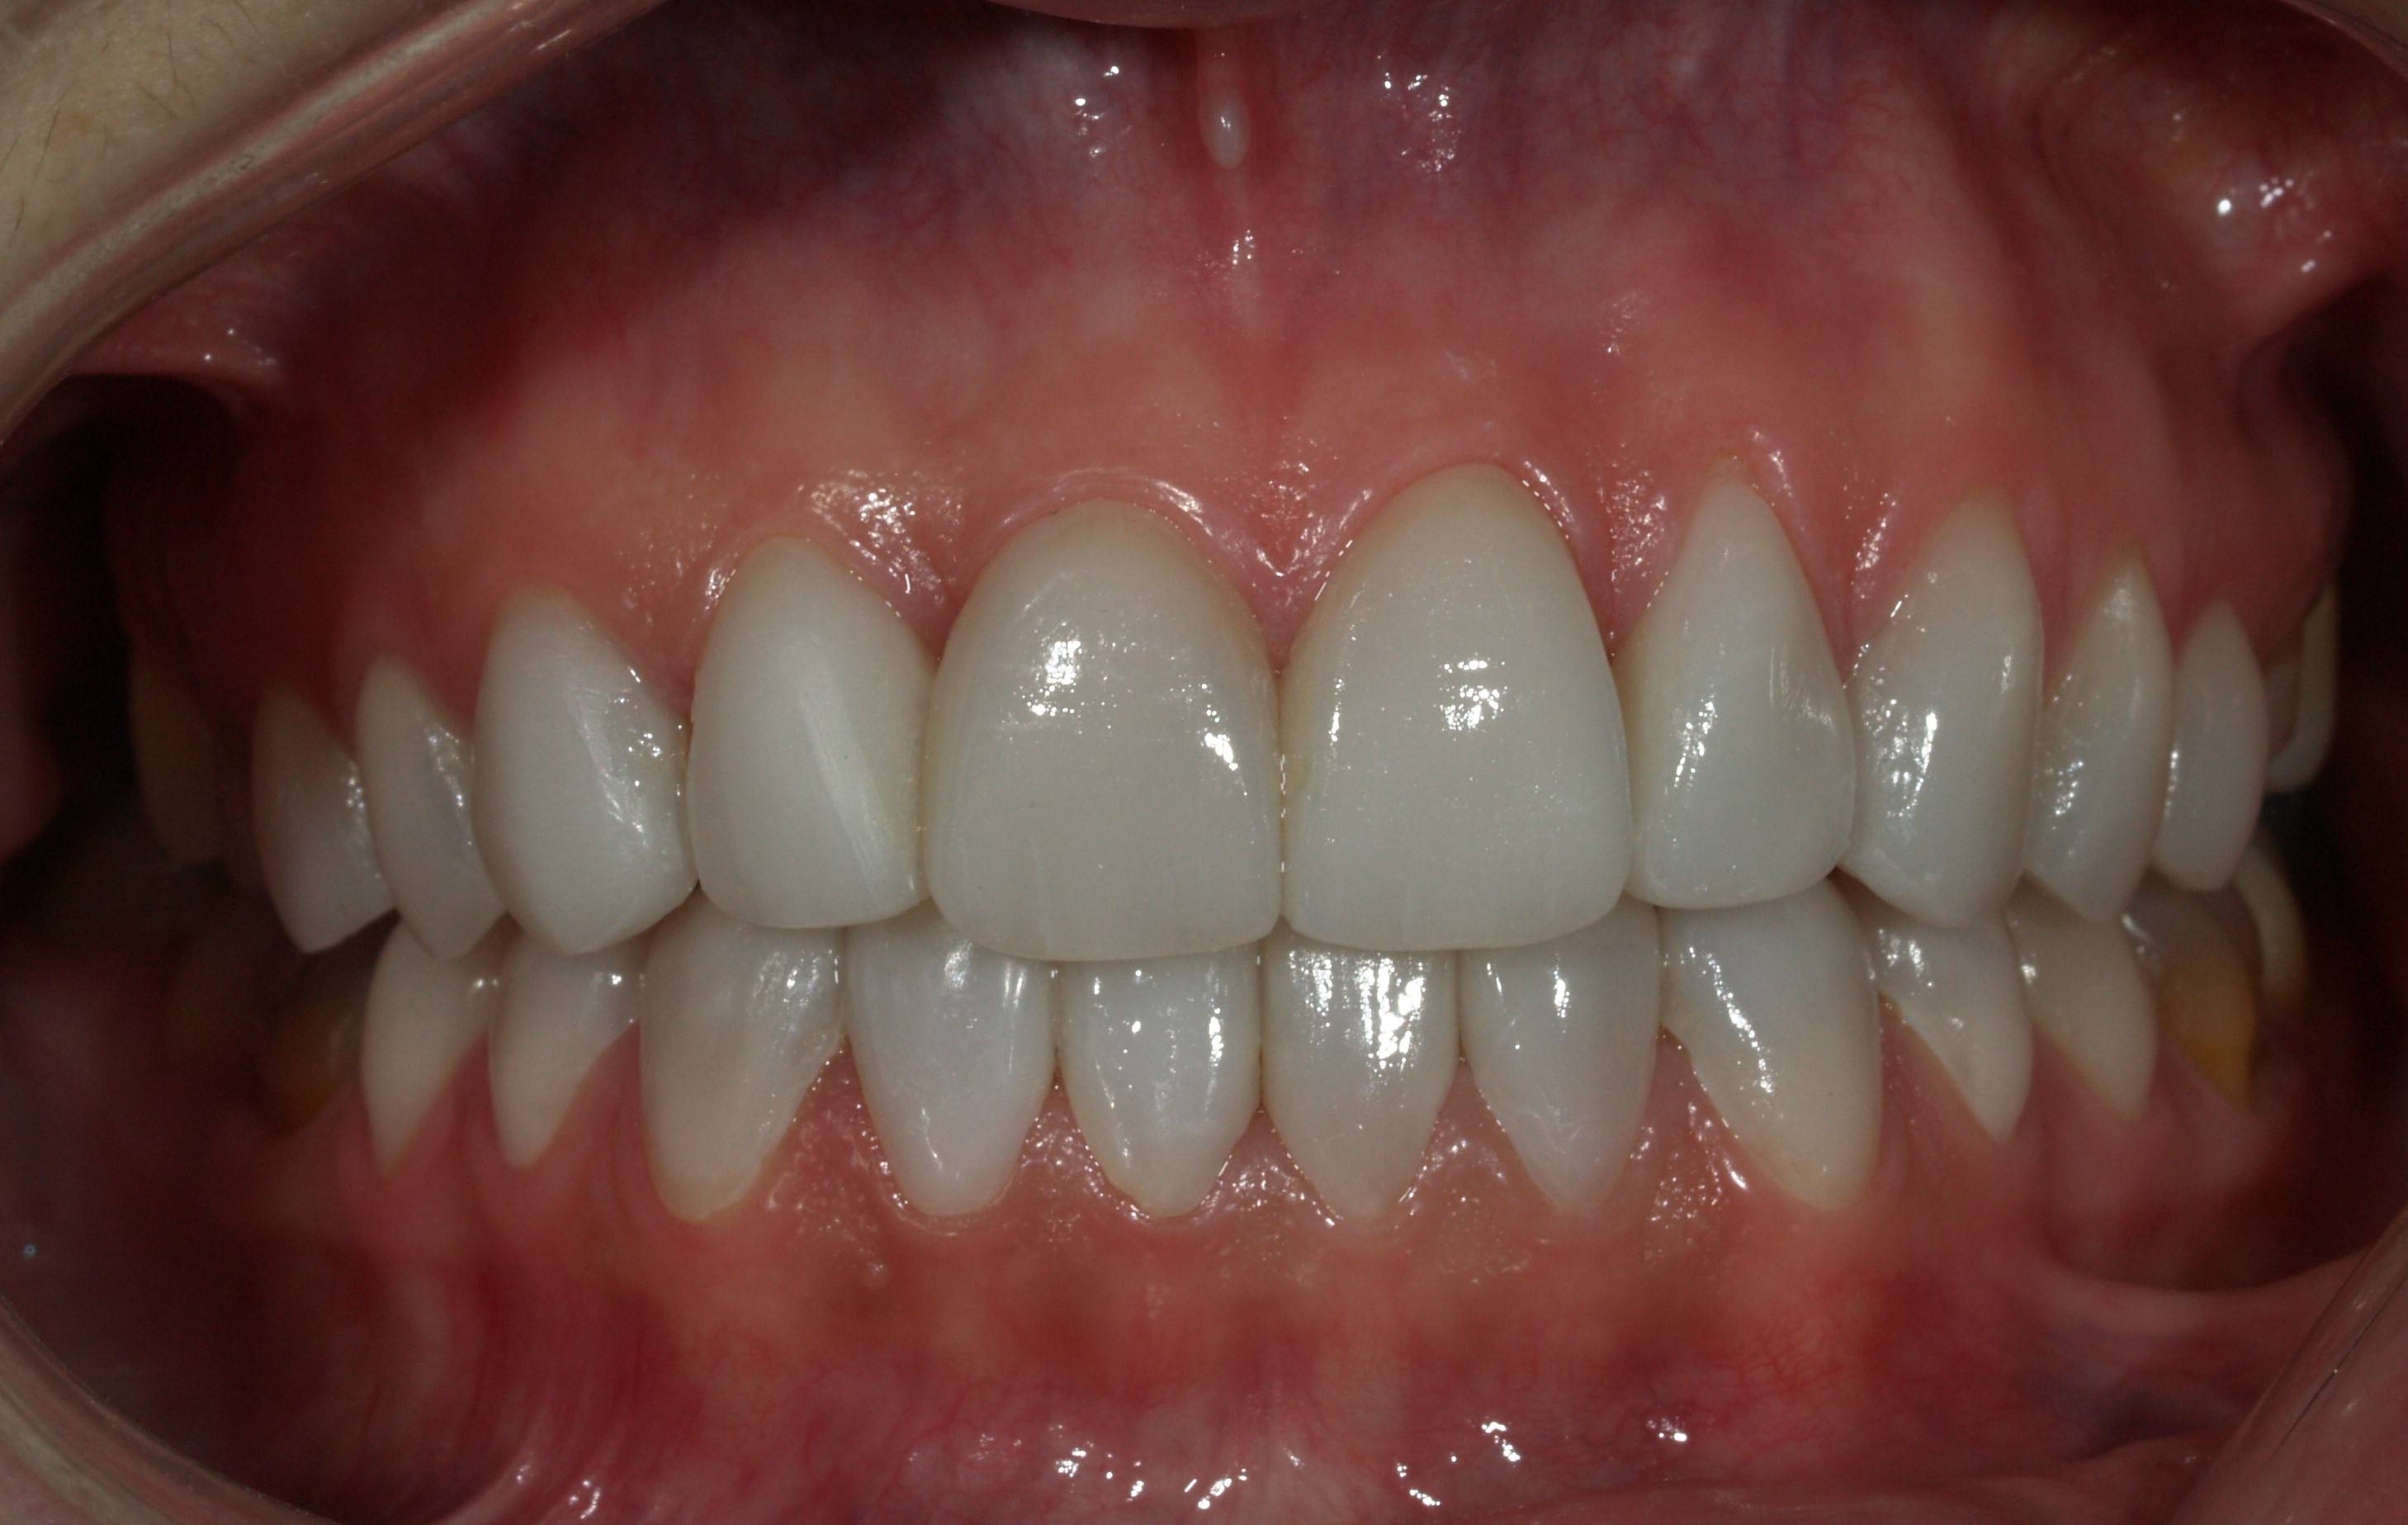

Blanqueamiento

Blanqueamiento - Antes Blanqueamiento - Después

ANTES

DESPUÉS